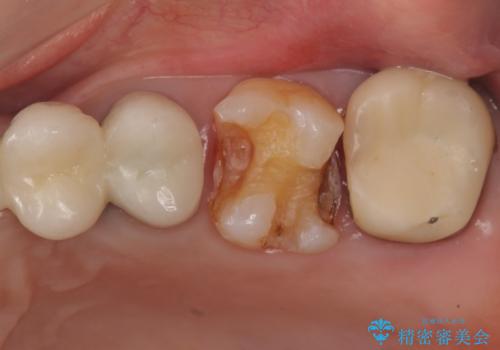

- 左上の奥歯がたまにしみるとのことで来院。視診・レントゲン画像より明らかに劣化した不適な修復物を確認しました。

同じ材料で同じように修復し直してもまた同じような予後になることが予想されるため、適合の良いセラミックインレーでの治療を提案させていただきました。

しかし向かい合わせになる歯の咬みこみが強く、インレーでは破折してしまうリスクが高いと予想し、より強固なクラウンで修復することになりました。